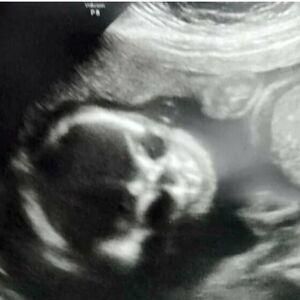

Otorinolaringolog koji je pregledao 9-godišnjaka video je krpelja pričvršćenog za bubnu opnu u uhu. Koža oko parazita koji se hrani je bila upaljena.

Dr Erik Valdman, šef pedijatrijske otorinolaringologije na Jejlu u Nju Hejvenu, prvobitno je pokušao da tradicionalno ukloni krpelja. Nažalost, ispostavilo se da je on duboko zagrizao bubnu opnu da se može ukloniti samo hirurški (pod opštom anestezijom).